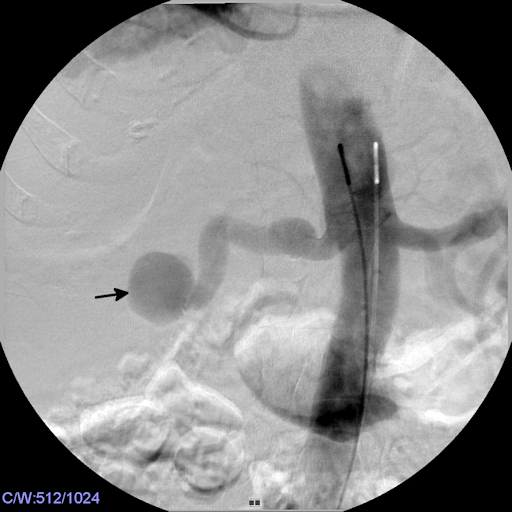

Institutional review board approval is not required at our institution for single-patient case reports.

The right common femoral artery was accessed in a retrograde fashion and a 5-F introducer sheath (Terumo Europe, Leuven, Belgium) was placed with Seldinger technique under local anaesthesia. An aortogram with power injection (15 ml/sec) via a 5F Nylex Pigtail Catheter (Cordis, Bridgewater, NJ, USA). Contrast agent: Imeron 300, Bracco, Konstanz, Germany) confirmed an aneurysm of the distal right residual renal artery and a giant AVF between the aneurysm and the inferior vena cava (Figure 2 [Fig. 2]).

Figure 2: The aortogram confirmed the large aneurysm (arrow) of the right renal pedicle.